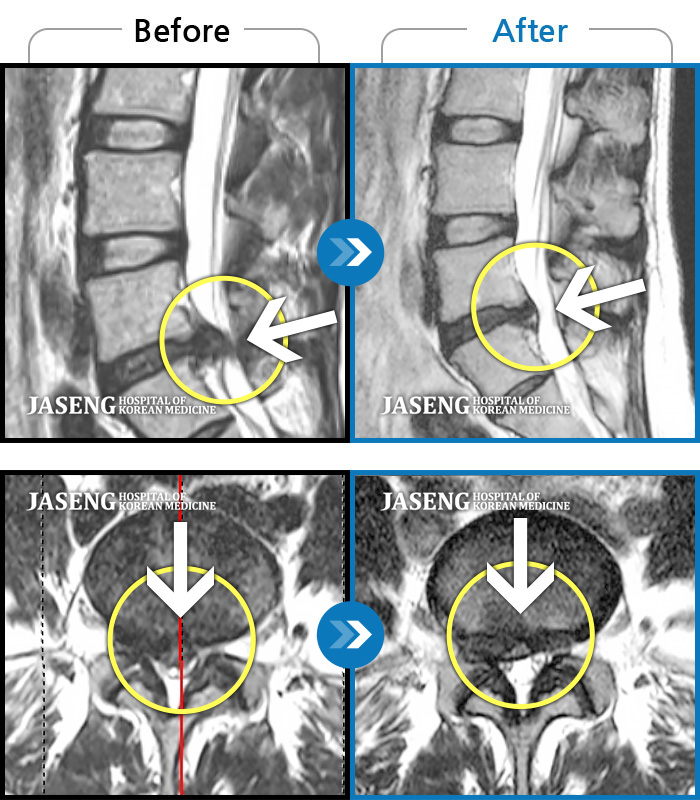

허리디스크

강남 · 이남우 원장

수년간 지속되어온 만성적인 허리통증이 최근 들이 치료에도 반응하지 않고 더욱 심해졌다.

촬영시기

2022.06.21 ~ 2024.08.19